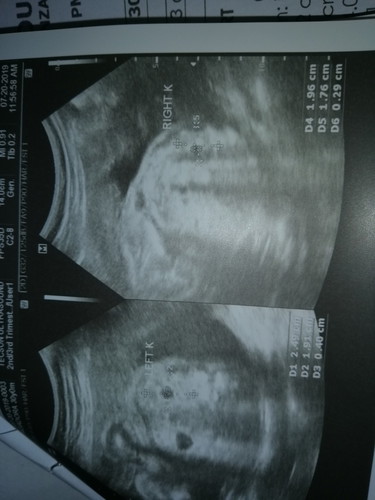

MONITOR RENAL PELVISES FOR SUBSEQUENT SCAN

Mga mamsh di talaga ako mapakali.. yan nakita sa CAS ko kahapon . my binanggit ung nag cas sken na prominent ung left kidney nia, saka di daw nakakaihi ng maayos sa loob kaya ganon daw , boy kasi gender ni baby. pls enlighten me po. kahapon pa kasi ako worried. sa 8 pa kasi balik ko kay Ob. no bash po pls